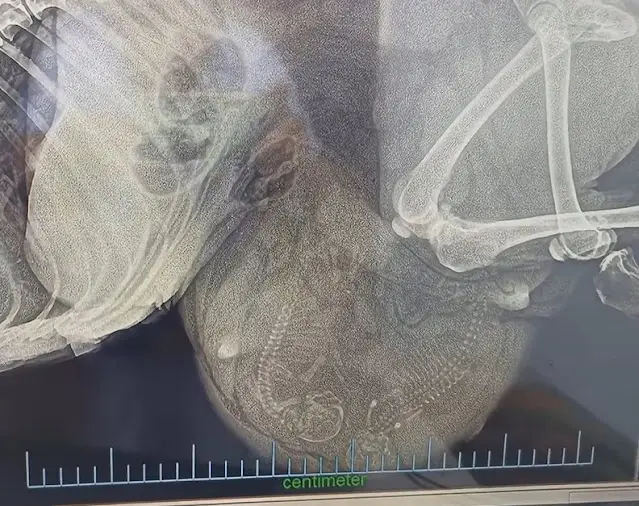

Time was against them, so the team rushed her to the veterinarian. Every moment felt critical, and their worry deepened with each passing second. When the ultrasound results came back, the rescuers were stunned—what they had mistaken for a tumor was actually something else entirely.

Inside her swollen belly were two tiny lives. Against all odds, this emaciated dog had been fighting not only for herself but also for her unborn puppies. Her collapse on the street was not a sign of giving up, but a mother’s desperate attempt to cling to life long enough to protect her babies.

The discovery brought both hope and urgency. She needed surgery right away if there was any chance to save her and the puppies.